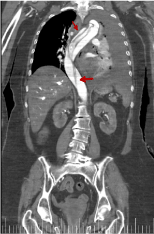

Figure 8. Coronal reconstruction image from thoracic-abdominal CT with i.v.c. in arterial phase. It shows the aortic flap in the entire aortic trajectory (red arrow)

We can see in figures 16 and 17 almost the entire trajectory of the aortic dissection, including the common iliac arteries.

Figure 16. Coronal reconstruction from thoracic-abdominal CT with i.v.c. in late portal phase that shows the range of the aortic dissection (red arrow)

Figure 17. Coronal reconstruction from thoracic-abdominal CT with i.v.c. in late portal phase that shows the range of the aortic dissection (red arrow)